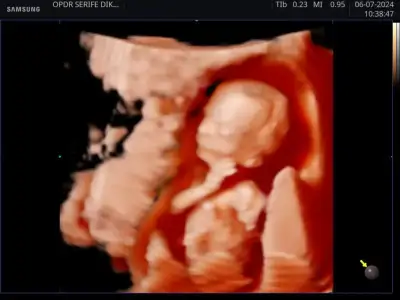

outoffit outoffit merhaba bizim cinsiyetimiz belli oldu, erkek🩵 🤗 bu da minik oğlan 🐞

Eklentiler

• 1000061540.webp

1000061540.webp

19,2 KB · Görüntüleme: 76